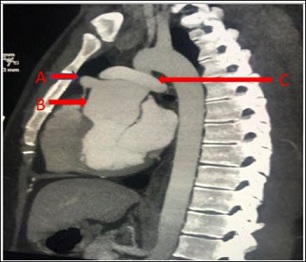

The chest pain was atypical in nature without any significant exertional dyspnea or syncope. He denied tobacco use but had been vaping for 4 years prior to presentation. On examination, vitals were stable. Auscultation of heart revealed a normal S1 and S2 without murmurs. The rest of the physical exam was within normal limits. Electrocardiogram showed sinus rhythm. Echocardiogram showed levocardia with normal ventricular systolic function and ejection fraction of 57%. Contrast computed tomography scan of the chest showed a 1.1x1.5x1.1 cm aneurysm of the proximal LAD artery (Figure 1). Findings were confirmed on Magnetic Resonance Imaging (Figure 2). Exercise myocardial perfusion imaging was also normal. The patient’s Adult Congenital Heart Disease Anatomical and Physiological classification was IIIA. Patient’s medical records were obtained and showed his LAD artery aneurysm diagnosis was madeaboutfiveyearsearlieratage13, and there was no interval progression since. After a multidisciplinary discussion, continued medical management was felt to be the best option for the patient with serial clinical follow-ups. On a 6-month follow-up, the patient continues to be doing well and has excellent functional capacity.

Figure 1: Cardiac CT A) Aneurysm of the proximal left anterior descending artery. B) Dilated aortic root. C) Pulmonary artery “draped” over the aorta post arterial switch surgery.